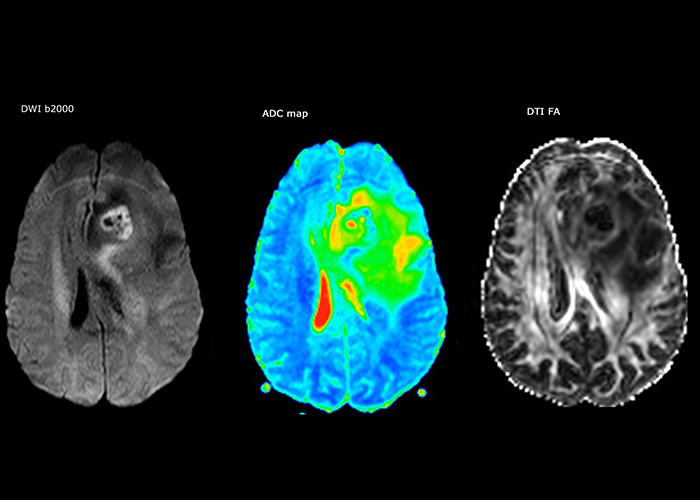

“In France, every stroke is usually imaged with MRI, not CT, even for emergency treatment.” “In France, stroke is usually imaged with MRI, not CT, even for emergency treatment. This is because MRI helps us directly visualize ischemia in the acute phase, but can also help rule out differentials such as MS and hematoma. In addition, we can assess the intracranial and extracranial vessels during the same examination,” says Dr. Savatovsky.

The first challenge in MRI of stroke is speed. The patient typically arrives from an ambulance in the MRI preparation room and the installation is done on a separate dock outside the scanner room. “The venous access is placed during the neurological examination. If the delay from the first symptoms allows the patient to receive thrombolysis we do a very fast examination that typically lasts about 11 minutes including the pre-scans. In the case of transient ischemic stroke we usually add ASL perfusion because in some symptoms with negative diffusion, ASL sometimes indicates a vascular origin.”

“Ingenia provides great flexibility in the parameters setting. We can tune a sequence the way we want,” says Dr. Savatovsky. “For example, in a stroke exam we use a FLAIR sequence of about two minutes instead of the four-minute FLAIR we use for MS. The diffusion is 30 seconds, the T2*-weighted scan is 30 seconds, the angiography scan time is less than one minute. Ingenia is a great scanner in that situation; even with these fast sequences we can achieve good images with good SNR. When the first sequence tells us that it’s not an ischemic stroke but a hemorrhagic stroke, we may switch to a time-resolved angiography to look for vascular malformations and venous thrombosis.

“Every center is different, but for me the ideal protocol for stroke includes diffusion weighted imaging, FLAIR, and fast susceptibility imaging,” says Dr. Savatovsky. “Our fast susceptibility weighted imaging takes 50 seconds, so it’s as fast as T2*-weighted imaging. It visualizes hemorrhage but also the clots. We also do 3D MR angiography that provides information on cervical and brain vessels. If the patient does not need immediate treatment, or if additional information is needed to decide on treatment, we might also add perfusion imaging and post-contrast T1-weighted imaging.”